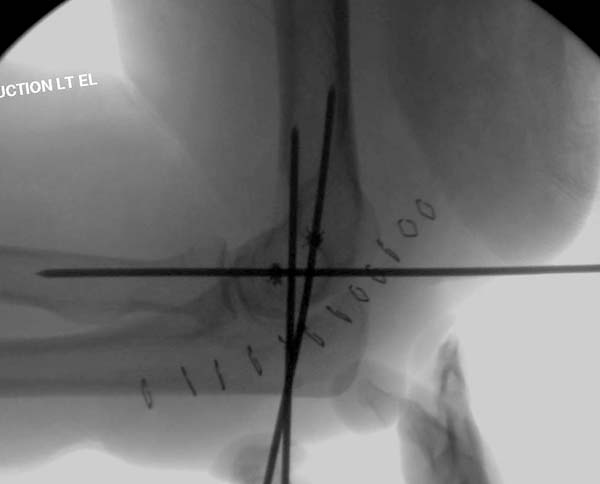

Снимки: 1-2 вывих, 4-5 вторичное смещение в гипсе, реконструкция

латеральной связки и капсулы 13-14, повторный вывих после реконструкции,

перевод в наш центр; 18-21 временная фиксация, 22-25 трансартикулярная

фиксация и нестабильная головка фиксирована спицами, 29-30 амбулаторно,

Имя     : 18 Elbow dislocation closed reduction SLU 3.JPG

Тип     : image/jpeg

Размер  : 24892 байтов

Описание: отсутствует

Url     : http://weborto.net:8080/pipermail/ortho/attachments/20131212/4b05a6a3/attachment-0008.jpeg